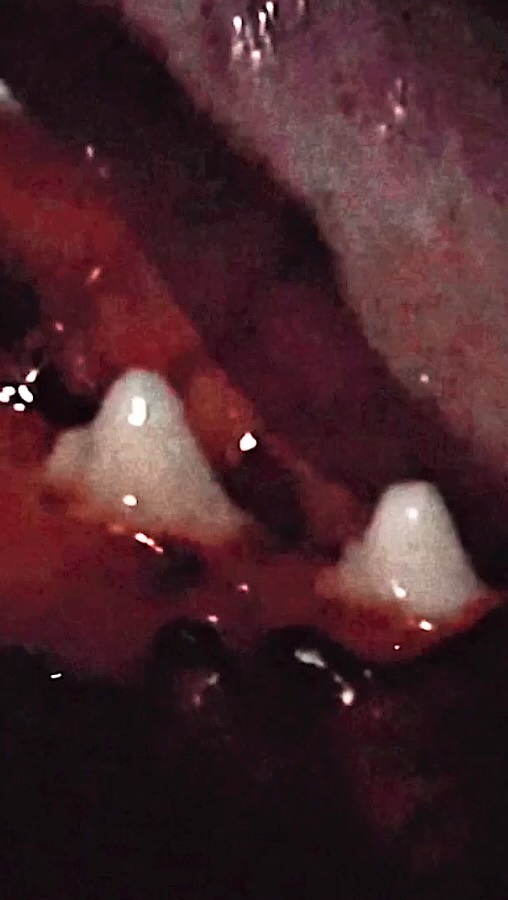

Los Artistas Médicos Científicos crean ilustraciones detalladas que representan conceptos médicos y científicos, ayudando en la educación y la investigación. Su representación hábil de temas complejos es crucial para libros de texto, revistas y presentaciones. Para ilustraciones médicas científicas profesionales en Londres, consulta a nuestros artistas expertos.